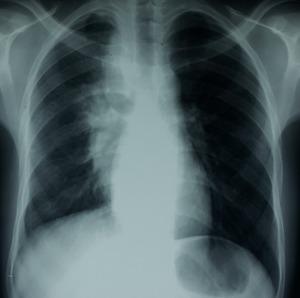

诺卡菌病是一种由诺卡菌属细菌引起的罕见但严重的感染,诺卡菌属属于放线菌目。如果诺卡菌病能够影响免疫功能正常的成年人,那么它通常是影响免疫系统较弱个体的疾病。肺部受累是最常见的表现形式,其正确的治疗基于诊断,但由于症状不具特异性且标本检查结果不明确,诊断往往会延迟。我们在此报告两例免疫功能正常患者的诺卡菌病病例。第一例是一名24岁有吸烟和酗酒史的男性,因胸痛和少量咯血持续两个月入院,伴有背部皮下瘘管性脓肿。影像学评估显示右纵隔-肺组织肿块,伴有相邻肋骨溶解及右侧椎旁组织播散。细菌学采样结果为阴性,于是对病变进行超声引导下活检,确诊为诺卡菌感染。第二例是一名22岁男性,8年前有胸膜结核病史,2011年有结核病复发(纵隔脓肿)。因基于慢性咳嗽、全身状况改变及肝脾肿大怀疑结核病复发而入院。胸部CT扫描显示有肺泡实变伴胸膜炎。住院期间出现了脓性皮下肿胀。脓液细菌学分析确诊为诺卡菌病。诺卡菌菌株对除黏菌素和复方新诺明外的所有抗生素均耐药。本研究旨在突出肺部诺卡菌病的临床和影像学特征,重点关注诊断和治疗方面的困难,尤其是在结核病高发且诺卡菌病发病率极低的国家。